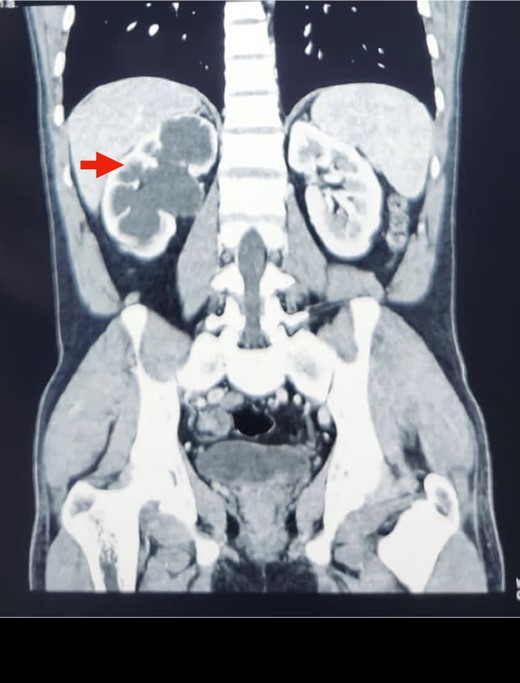

A midline incision was given, and the abdomen was opened from 4 cm below the xiphisternum to 3 cm above the pubic symphysis. The ascending colon along with the hepatic flexure was completely mobilized medially to expose the retroperitoneum. Careful dissection was done to identify the IVC and its the relations to the right ureter. The proximal dilated ureter and right pelvicalyceal system were identified, and dissection was continued laterally. The ureter was traced and noticed to course behind the IVC at the level of the L2–L3 vertebra, exiting to lie medially in the groove between the IVC and the aorta (Fig. 3). The ureter was divided proximal to the point where it coursed behind the IVC until it came out medial to IVC (Fig. 4). The retrocaval segment was brought anteriorly, resected from the normal distal ureter, and ureteropelvic anastomosis was done using 3–0 Polyglactin sutures lateral to the IVC (Fig. 5). This procedure eliminated the compression on the ureter. An abdominal drain was placed.

Intraoperative image showing pelviureteric anastomosis after resection of retrocaval part of the ureteric segment.